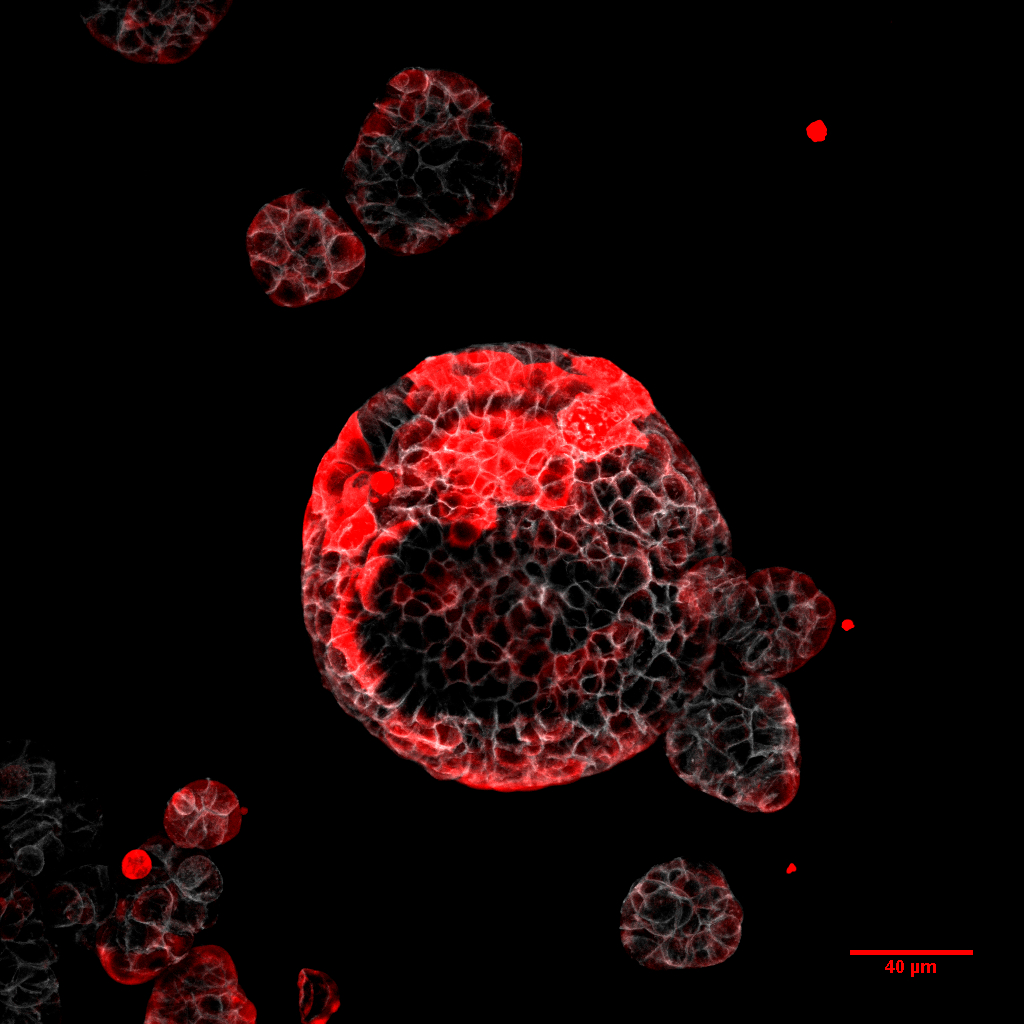

Els científics han generat un nou model experimental en ratolins que recrea el procés dels pacients amb recaigudes i han desenvolupat una metodologia que permet aïllar una fracció minúscula de cèl·lules tumorals disseminades ocultes a l’organisme. “El nostre model, molt semblant al progrés de la malaltia en pacients, ens ha permès caracteritzar el tumor primari i la dinàmica de la malaltia residual. Hem estudiat des de micrometàstasis de 3 o 4 cèl·lules, a metàstasis mitjanes, o fins i tot més grans, i hem caracteritzat com evoluciona cadascuna durant la progressió de la malaltia”, ha afirmat Adrià Cañellas-Socias, primer autor de l’estudi a l’ACN.

La investigació ha permès determinar que les cèl·lules responsables de la recaiguda són capaces de desprendre’s del càncer al còlon, migrar fins al torrent sanguini, arribar al fetge i romandre ocultes durant un temps després de la cirurgia. L’estudi conclou, a partir d’experiments amb ratolins, que eliminar aquestes cèl·lules mitjançant tècniques genètiques és suficient per prevenir la formació de metàstasi. Segons els investigadors, després de la cirurgia i la quimioteràpia, les cèl·lules tumorals residuals ara descobertes romanen ocultes principalment al fetge o al pulmó, i són invisibles a les tècniques diagnòstiques utilitzades a la clínica.